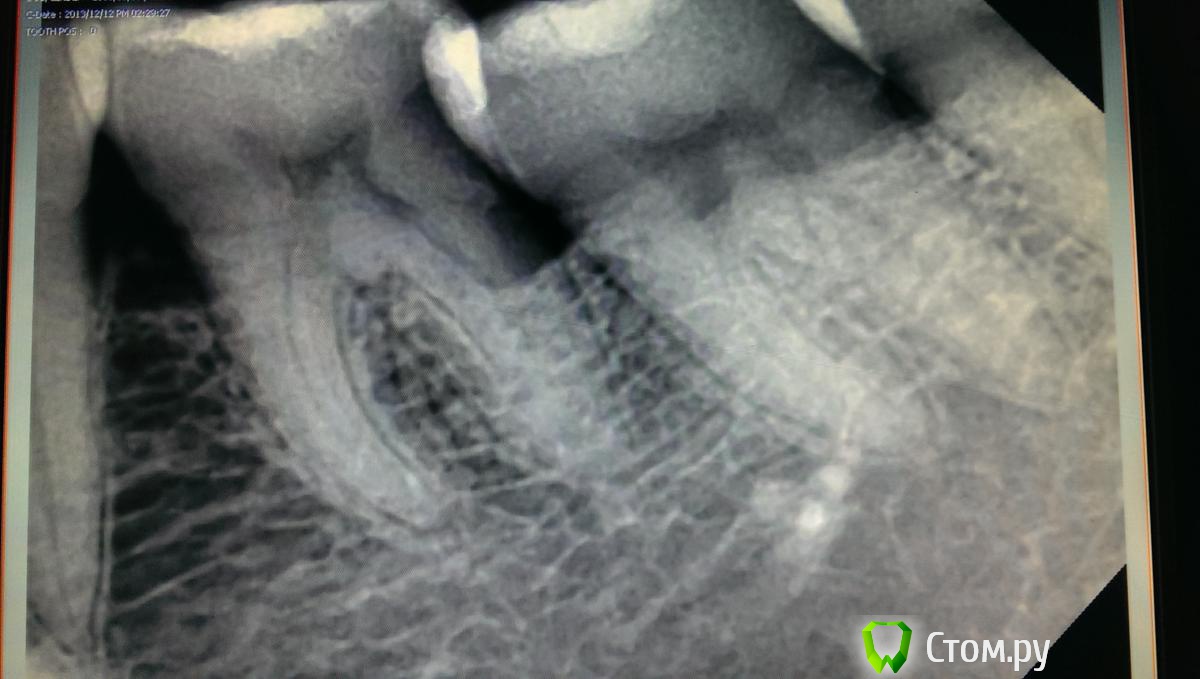

art700 Опубликовано 16 января, 2014 Поделиться Опубликовано 16 января, 2014 Вобщем спрошу здесь, дабы не создавать новой темы. Пациентка - ассистенка клиники, попала ко мне уже после одного доктора терапевта, решил посмотреть ее, ибо боли как говорят. Зуб 36 мучает, изначально беспокоила боль при чистки, запах ну и т.д. Как я понял для начала решили убрать плотный контакт с зубом 3.7, стало легче, но через пару дней появилась сильная боль на холодное, только на холодное причем. Думаю депульпировать уж или есть варианты какие? Снимок практически двухнедельной давности, сейчас по ее словам должно быть тоже самое, т.к практически ничего не делали, но фиг его знает. Вобщем болит. Ссылка на комментарий

Л Ю С Я Опубликовано 17 января, 2014 Поделиться Опубликовано 17 января, 2014 Вобщем спрошу здесь, дабы не создавать новой темы. Пациентка - ассистенка клиники, попала ко мне уже после одного доктора терапевта, решил посмотреть ее, ибо боли как говорят. Зуб 36 мучает, изначально беспокоила боль при чистки, запах ну и т.д. Как я понял для начала решили убрать плотный контакт с зубом 3.7, стало легче, но через пару дней появилась сильная боль на холодное, только на холодное причем. Думаю депульпировать уж или есть варианты какие? Снимок практически двухнедельной давности, сейчас по ее словам должно быть тоже самое, т.к практически ничего не делали, но фиг его знает. Вобщем болит.В чем причина деформации зубного ряда? Есть ОПТГ? Ну депульпируете, но резорбция то будет прогрессировать если не убрать причину. Антагониста у 6 наверное нет? Смотрите какой карман сформировался. Как там с гигиеной? Вобщем, смотрите в полость рта. Ссылка на комментарий